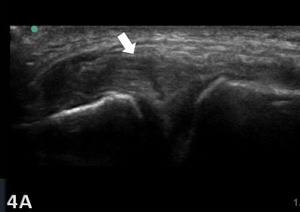

Ultrasound Technique and Diagnostic Criteria for MCL Injuries

MSK-US is highly effective in identifying the presence and severity of MCL injuries. The ligament’s superficial location makes it readily accessible for US examination, which can be enhanced with high-frequency linear transducers to produce detailed soft-tissue images. Dynamic imaging during knee flexion and extension, not possible with MRI, further improves the diagnostic accuracy of US by demonstrating the static functional integrity of the MCL. The examination involves scanning in both longitudinal and transverse orientations, assessing the ligament for echotexture, continuity, and any associated anechoic (fluid) collections indicating acute injury. Diagnostic criteria for MCL injuries are based on ligament thickness, loss of the normal fibrillar pattern, and the presence of preligamentous fluid. One tip when assessing the femoral insertion of the superficial fibers of the MCL is gently tilt the probe along the MCL curved course to avoid the anisotropic effect of a false hypoechogenicity.18